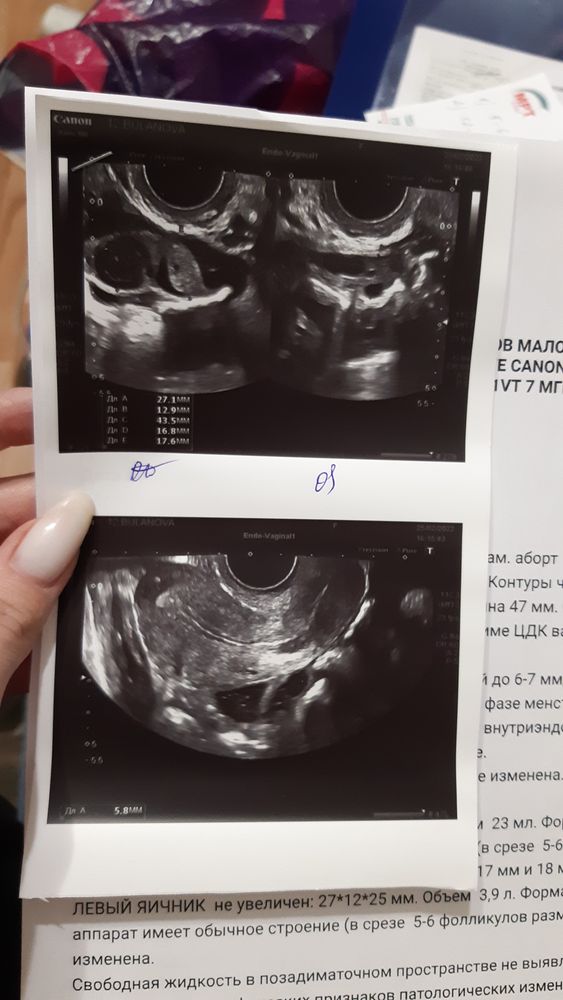

По контрольному узи, делала 2 раза все хорошо